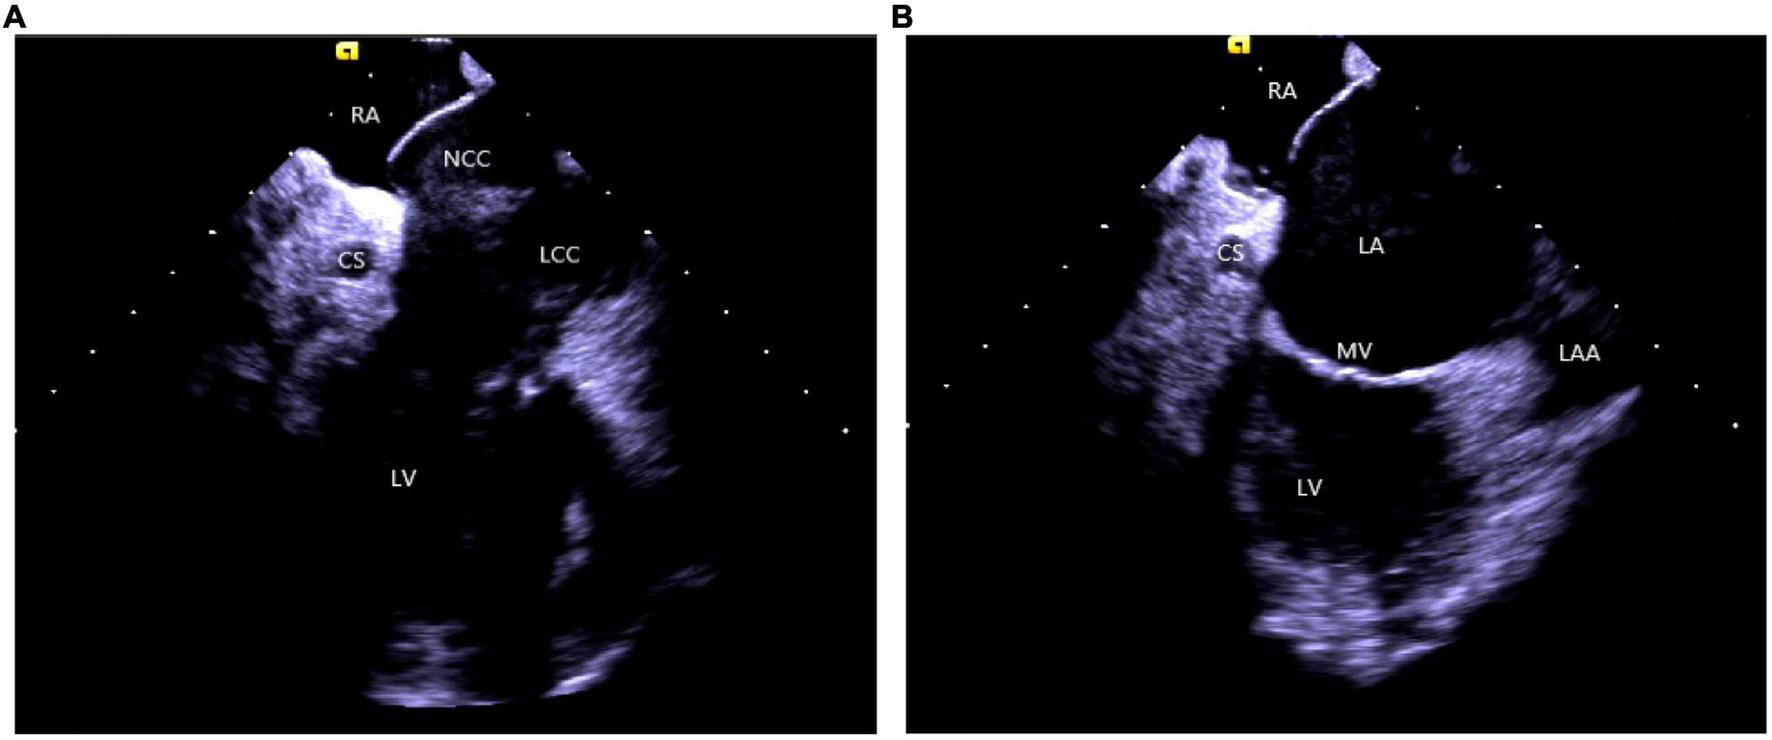

(2) Right atrium operation and view: After positioning the ICE catheter in the mid-right atrium (RA) through the inferior vena cava, the catheter was rotated so that the ultrasound probe points to the center of the tricuspid valve (TV), thereby reaching the HomeView position. This important position provided imaging of the RA, TV, right ventricle (RV), aortic long axis, non-coronary, and right coronary cusps, as well as a small part of the right ventricle outflow tract (RVOT) (Figure 1). From the HomeView position, a clockwise rotation exhibited the RV long axis model, showing the RA, coronary sinus, non-coronary and left coronary cusps, and part of the left ventricle (LV). Further clockwise rotation identified the left atrium (LA) and displayed the LA, RA, coronary sinus, left atrial appendage, mitral valve, and LV, respectively (Figure 2).

FIGURE 2

(A) The clockwise rotation from the HomeView position. (B) The clockwise rotation from the A position. RA, right atrium; CS, coronary cusp; LV, left ventricle; NCC, non-coronary cusp; LCC, left coronary cusp; RVOT, right ventricular outflow tract; LA, left atrium; MV, mitral Valve; LAA, left atrial appendage.